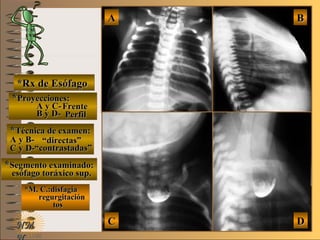

*Rx de Esófago*Rx de Esófago

**Proyecciones:Proyecciones:

A y C-A y C-

B y D-B y D-

**Técnica de examen:Técnica de examen:

A y B-A y B-

C y D-C y D-

**Segmento examinado:Segmento examinado:

*M. C.:disfagia*M. C.:disfagia

regurgitaciónregurgitación

tostos

NMNM

BBAA

DDCC

FrenteFrente

PerfilPerfil

““directas”directas”

““contrastadas”contrastadas”

esófago toráxico sup.esófago toráxico sup.

A-A-El examen es normal o patológico?El examen es normal o patológico?

Examen patológico de esófago toráxico su-Examen patológico de esófago toráxico su-

perior sin contraste (directa), con relleno yperior sin contraste (directa), con relleno y

en proyecciones de frente y perfilen proyecciones de frente y perfil

B-B-La patología es congénita o adquirida?La patología es congénita o adquirida?

Patología congénita en neonatoPatología congénita en neonato

C-C-Puede describir la o las imágenes patológicas?Puede describir la o las imágenes patológicas?

**OpciónOpción

de volverde volver

a ver lasa ver las

imágenesimágenes

Se identifica una “bolsa ciega” en el tercio su-Se identifica una “bolsa ciega” en el tercio su-

perior del esófago toráxico sin comunicaciónperior del esófago toráxico sin comunicación

con las vías aéreas, corresponde a una de lascon las vías aéreas, corresponde a una de las

variantes de atresia de esófagovariantes de atresia de esófago

**Opción avanzada para volver a ver las imágenes con reparosOpción avanzada para volver a ver las imágenes con reparos

A y C- FrenteA y C- Frente

B y D- PerfilB y D- Perfil

A y B- “directas”A y B- “directas”

C y D- “contrastadas”C y D- “contrastadas”

““bolsa ciega”bolsa ciega”

sin contrastesin contraste

con contrastecon contraste

volvervolver